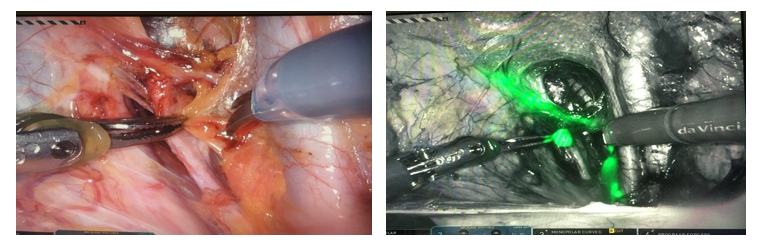

without dye3

Read more about "without dye3"... -

green dye2

Read more about "green dye2"... -